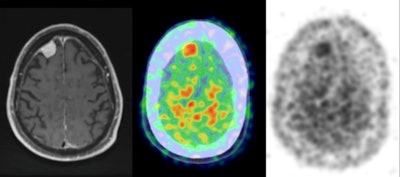

With its ability to achieve a high level of specificity, the combination of carbon-11-labeled Pittsburgh Compound B (PiB) with PET imaging is showing early promise in distinguishing meningiomas from other intracranial tumors, according to a study presented recently at RSNA 2016.

Researchers from the Mayo Clinic in Rochester, MN, are optimistic that PiB-PET could become a sensitive marker for intracranial meningioma and foster appropriate patient triage and treatment, without the need for invasive testing and the associated potential morbidity.

"The benefit with PiB so far seems to be its specificity," said lead author and neurologist Dr. Derek Johnson. "Meningiomas demonstrate activity on PiB-PET with high-level uptake that is specific for a variety of meningiomas."

The researchers retrospectively studied patients who underwent PiB-PET/CT at the Mayo Clinic between March 2006 and September 2015. They reviewed 2,472 patient records to identify those with intracranial tumors at least 5 mm in thickness and seen on contrast-enhanced MRI scans. Tumors also had to be confirmed by available pathology or by imaging characteristics as interpreted by board-certified neuroradiologists.

Of the 2,472 patients, 45 (1.8%) met the criteria for having a probable or confirmed intracranial tumor. There were 29 cases of meningioma (64%), as well as seven patients with vestibular schwannoma, four with pituitary macroadenoma, two with metastatic disease, two with an intraventricular mass, and one epidermoid tumor.

PiB uptake was significantly greater among the 29 patients with meningiomas, who had a mean maximum standardized uptake value (SUVmax) of 2.05 (standard deviation, 1.37). The second highest mean SUVmax was 1.40 (standard deviation, 0.72) for metastatic disease, followed by 1.37 (standard deviation, 0.54) for intraventricular masses.

Meningiomas also greatly differed in a lesion-to-cerebellum PiB uptake comparison. The mean SUVmax ratio for meningiomas was 2.12 (standard deviation, 0.70), compared with the second-highest result of 1.39 (standard deviation, 0.24) for intraventricular masses.

Lesion-to-cerebellum ratios above an optimum SUVmax ratio of 1.65 with an area under the curve (AUC) value of 0.91 accurately indicated meningioma. Results below the cutoff ratio indicated nonmeningiomas. For results at or above this ratio, sensitivity was 76%, specificity was 100%, positive predictive value was 100%, and negative predictive value was 70%.